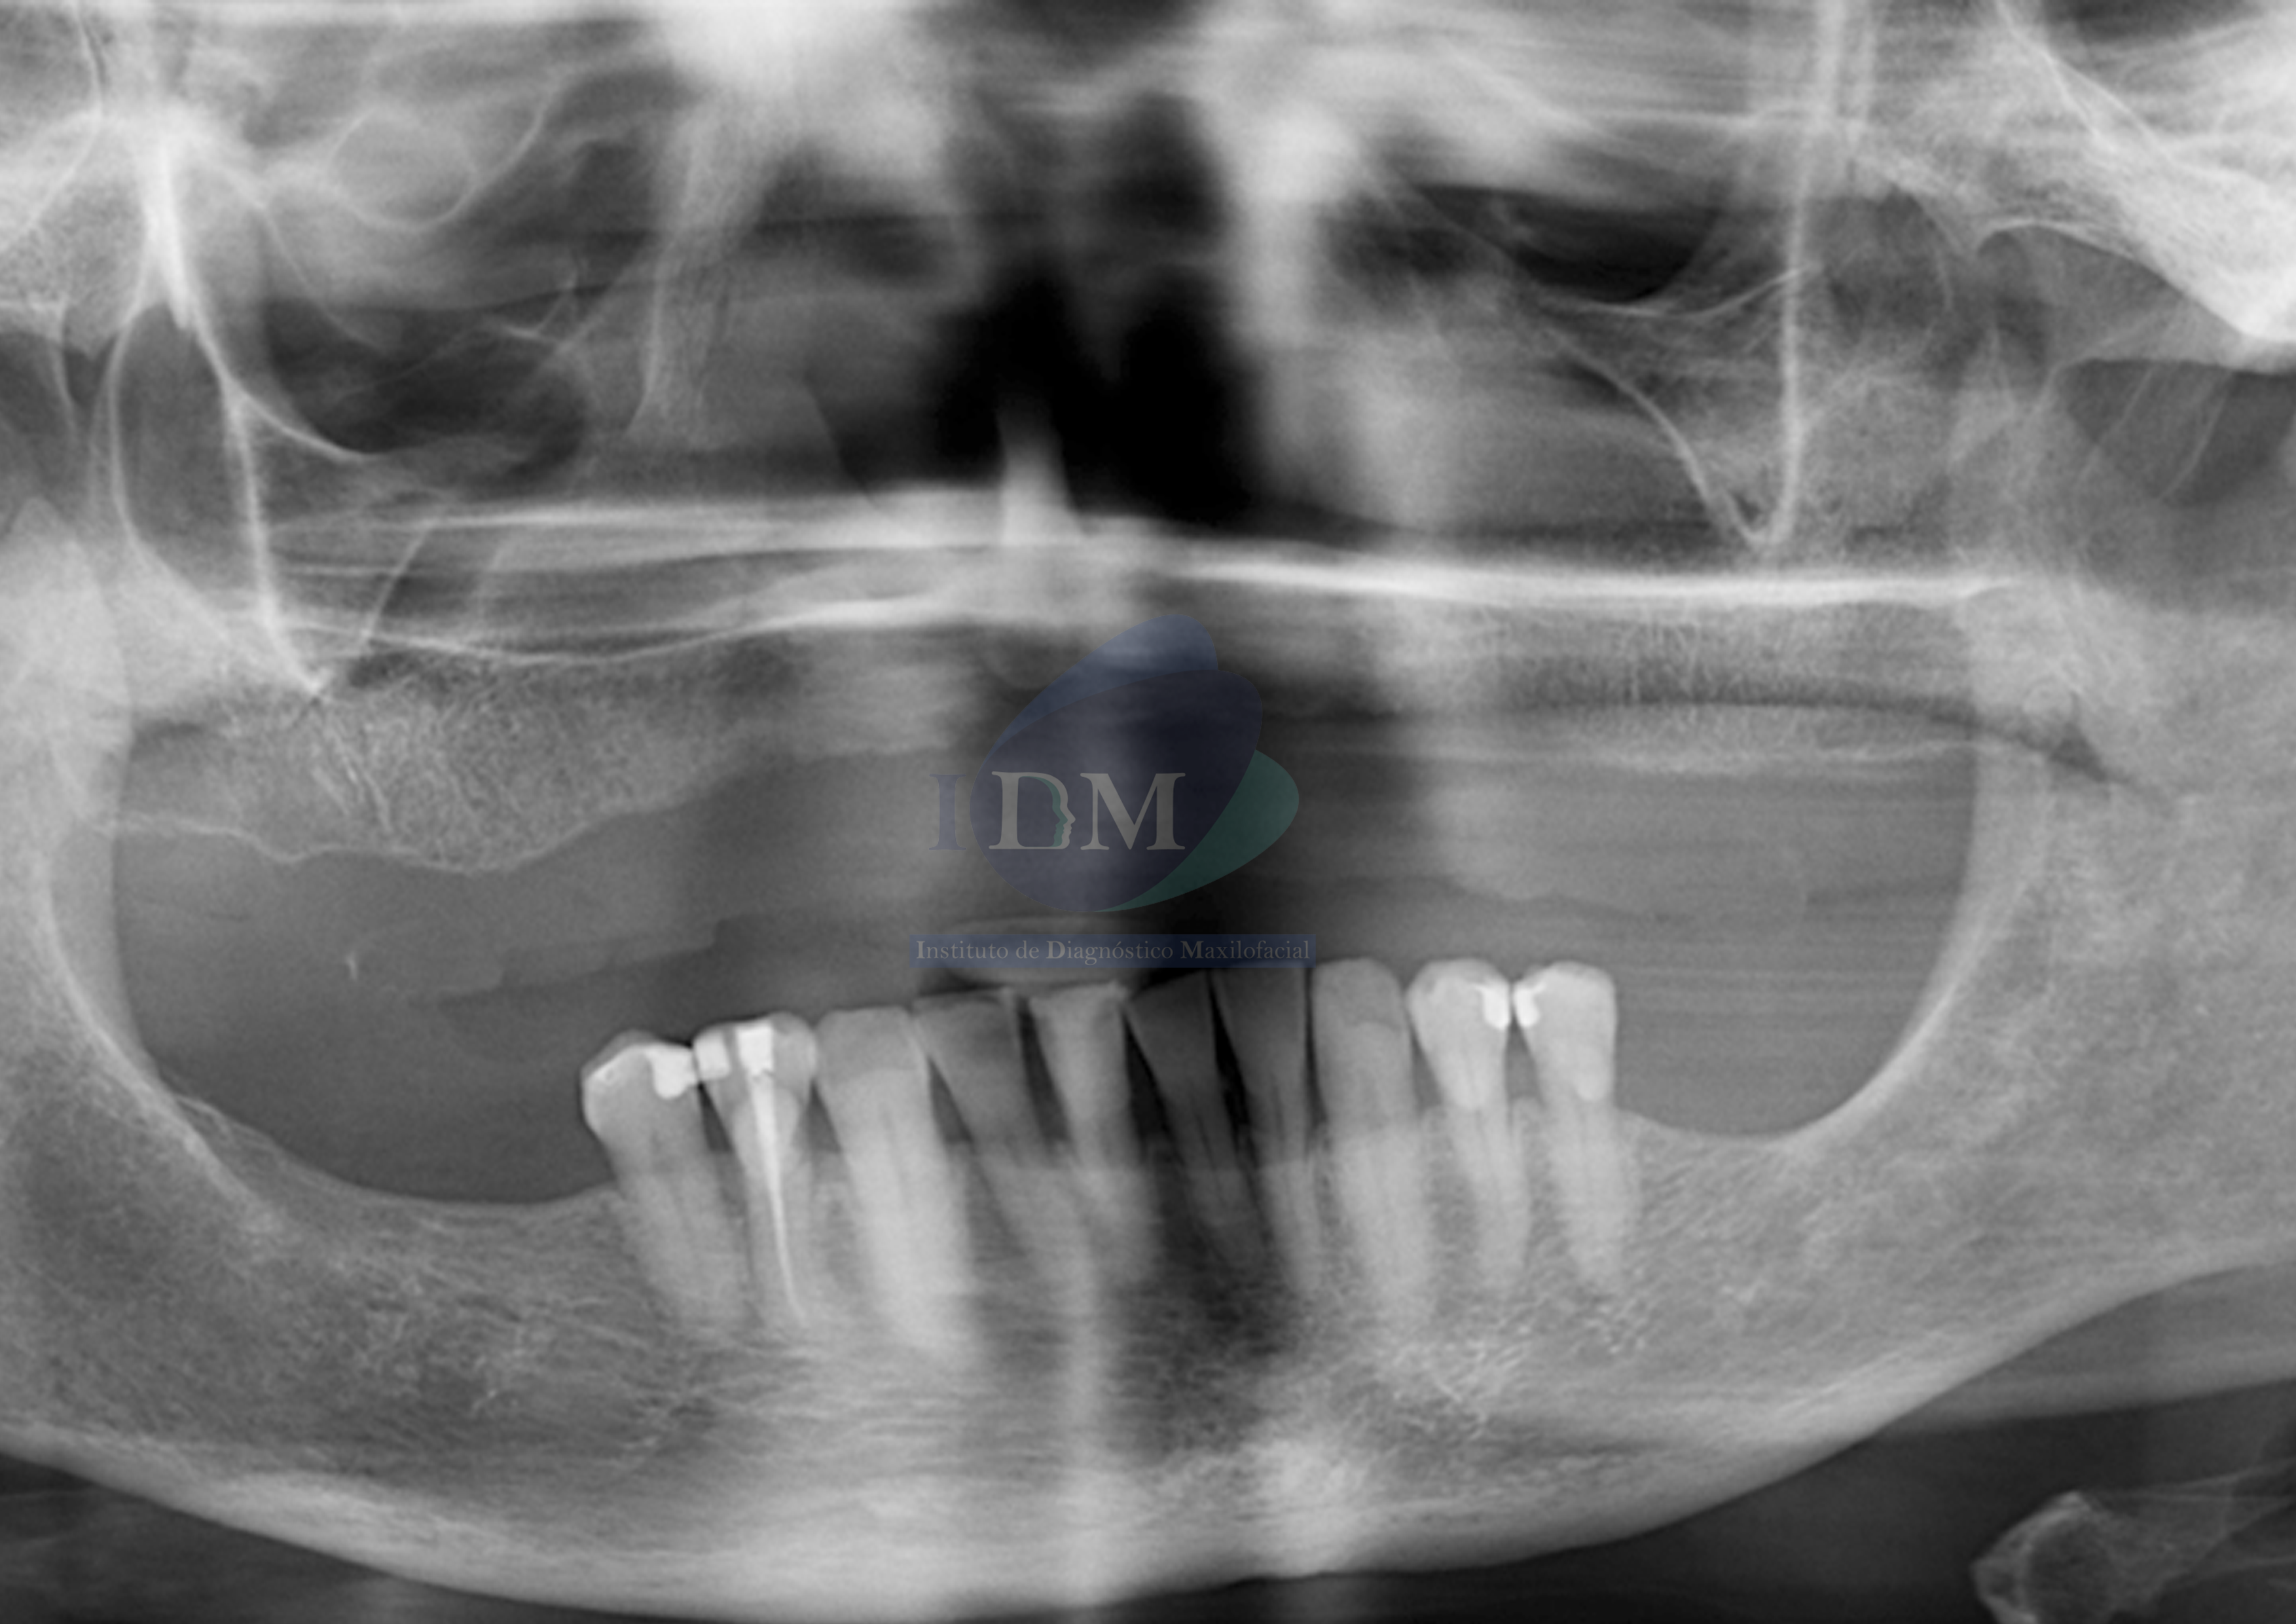

Paciente de sexo femenino acude para realizarle estudios imagenológicos con la finalidad de una diagnostico general.

A la evaluación de la radiografía panorámica se observa paciente Edéntulo total del maxilar superior, piezas dentarias del maxilar inferiores con múltiples restauraciones coronarias, reabsorción ósea del proceso alveolar y la pieza 44 con obturación de conducto.

Radiografia Panorámica